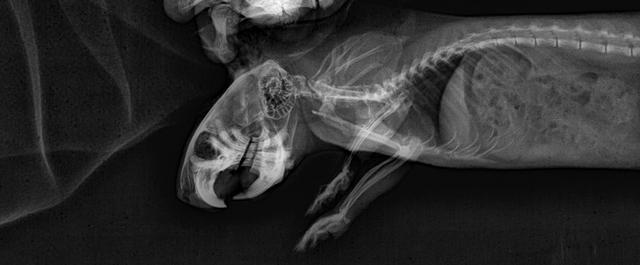

Приговор Малокклюзия генетическая.

После проведённых анализов, нарушений сбоя работы организма не нашли.

Вывод один-генетическая наследственная патология.

К сожалению Юкатана пришлось усыпить.

Корень зуба пророс в носовой пазух, животному было тяжело дышать, и оно испытывало боли.

Ямато пока поживёт на обезболивающих, у него чуть «лучше» обстоят дела , но это временно к сожалению.

Около месяца назад мне поступила информация от Фроловой о том, что у одного из ее мальчиков, рожденного в моем питомнике, Юкатана, диагностировали неоперабельную малокклюзию и его планируют усыплять.

Я стала более тщательно наблюдать за родителями мальчика. И у папы Чизкейка обнаружила неравномерно сточенные резцы. Поскольку зверю проблема дискомфорта не доставляла, а в разведении он не участвовал уже год и участие его пока не планировалось, я решила посетить врача в ближайшее свободное время. Но, в связи с последними бурными обсуждениями данного вопроса и с тем, что по словам Фроловой, подобное заболевание возникло и у Ямато, еще одного сына Чизкейка от другой матери, я перенесла наш визит к врачу, и мы были там сегодня.

Чизкейку (http://degu.by/site/genbasa/?id=34 ) поставлен диагноз: Малокклюзия, дентальная болезнь, стоматит.

Мальчик официально выведен из разведения на основании поставленного диагноза.

По его мнению генетические проблемы в области стоматологии проявляются в первые месяцы после рождения, иногда чуть позже, но всегда до достижения дегу возраста 1 год.

У Чизкейка озвучена именно такая причина. Воспаление десны (возможно стоматит), зверь перестал пользоваться одной стороной при жевании и это отразилось на состоянии резцов. Корни также отросшие.

Корни не прорастают сами по себе. Для этого должна быть проблема внутри рта. Зверь жует меньше обычного из-за болевых ощущений, зубы не стачиваются, становятся длиннее нормы и при жевании зубы давят друг на друга, из-за этого происходит продавливание корней вглубь.